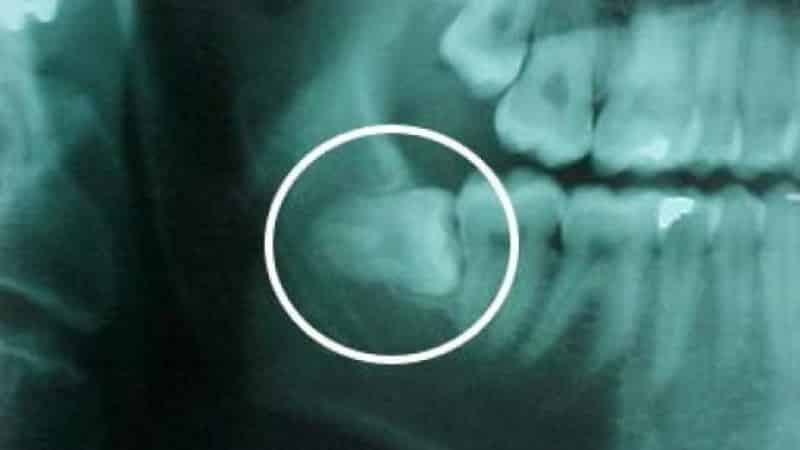

В таких случаях необходимо незамедлительно обратиться к врачу, сделать рентгеновский снимок и провести лечение или удаление зуба мудрости, чтобы предотвратить осложнения. Стоматологи при лечении таких патологий вскрывают слизистую оболочку, промывают полость и назначают противовоспалительные препараты. В некоторых случаях, при повторном воспалении, может потребоваться удаление зуба до его полного прорезывания. Еще одной распространенной проблемой во время роста зуба мудрости является появление кариеса.

Основная причина возникновения этого заболевания связана с недостаточной гигиеной в труднодоступной области роста зуба мудрости, и болезнь может быстро распространиться на соседние зубы из-за плотного прилегания. Если нет внешних признаков воспаления, рекомендуется сделать рентгеновский снимок, чтобы узнать о правильности роста зуба и необходимости его удаления.

- Ретинированный зуб мудрости, который не может прорезаться из-за неправильного расположения в челюсти и упора в соседние зубы.